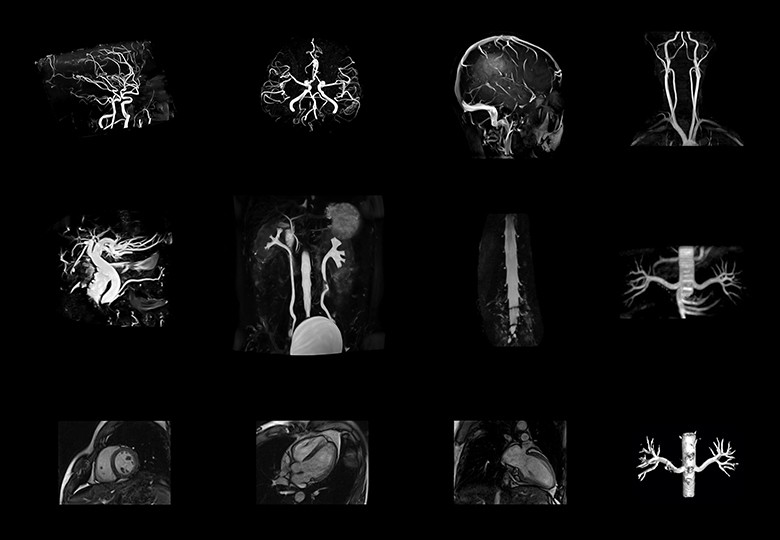

Album d'images cliniques

• Angio+Hydro